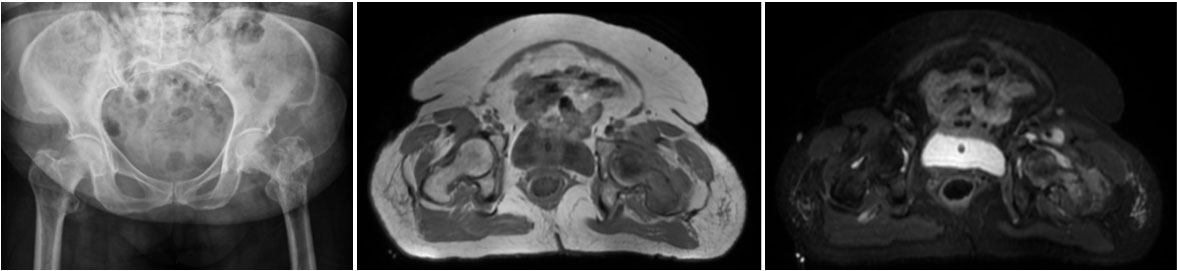

Ameliyat Öncesi: Röntgende sol proksimal femurda litik lezyonlar, MR’da ayrıca kemiğin dışına taşmış tümörün yumuşak doku komponenti görülmekte